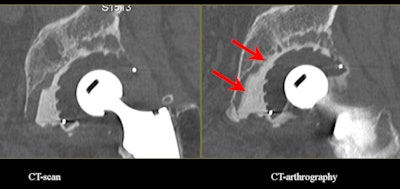

![]() |

| Acetabular loosening. CT arthrography clearly shows the diffusion of contrast medium around the cement in zones II and III. (Provided by Prof. Alain Blum) |